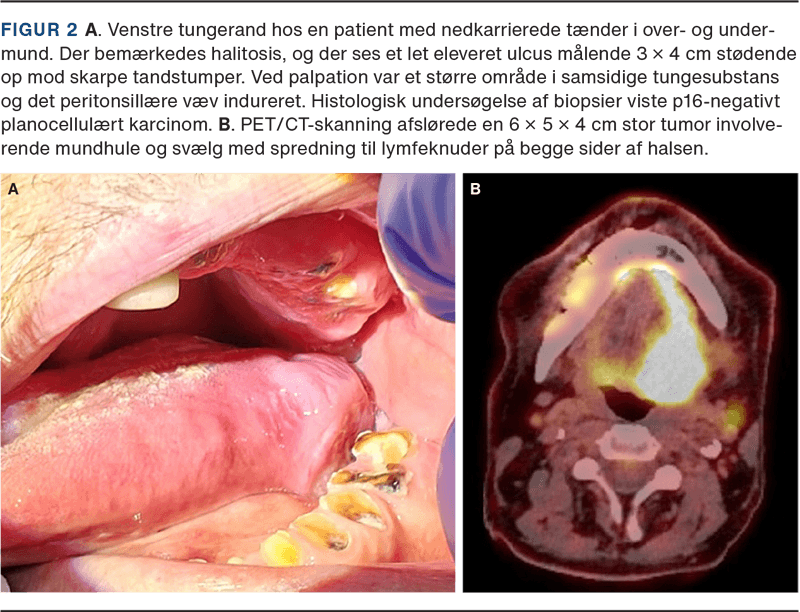

PCC kan vokse ned i vævet og fremtræde som sår (endofytiske/ulceroinfiltrative), vorter med nubret overflade (verrukøse) eller som fastelastiske gevækster (eksofytiske). I alle tilfælde kan området være let blødende, se Figur 2 og Figur 3.

Smerter i mundhulen eller ensidige øresmerter, blødning fra munden, svie og smerte ved fødeindtag, synkebesvær (dysfagi), dårlig ånde (halitosis) og hævelse på halsen er hyppige ledsagesymptomer. Fælles for disse er, at der kan være benigne årsager til symptomerne. Tandlægevurdering bør foretages ved mistanke om tryksår fra protese, skarpe kanter på tænder, fyldninger, broer eller implantater. Sår i mundhulen heler typisk op inden for to uger, hvis relevante udløsende årsager som infektion og gnavende proteser elimineres.